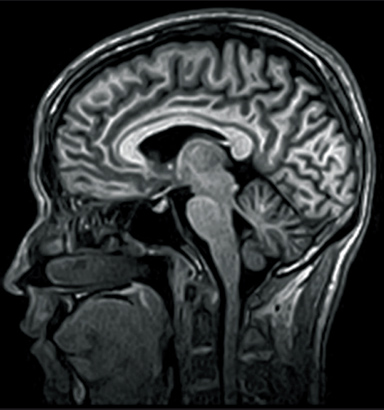

3D-GEIR